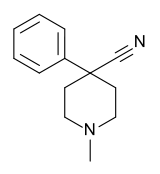

4-Phenylpiperidines

Pethidines (meperidines)

Structures